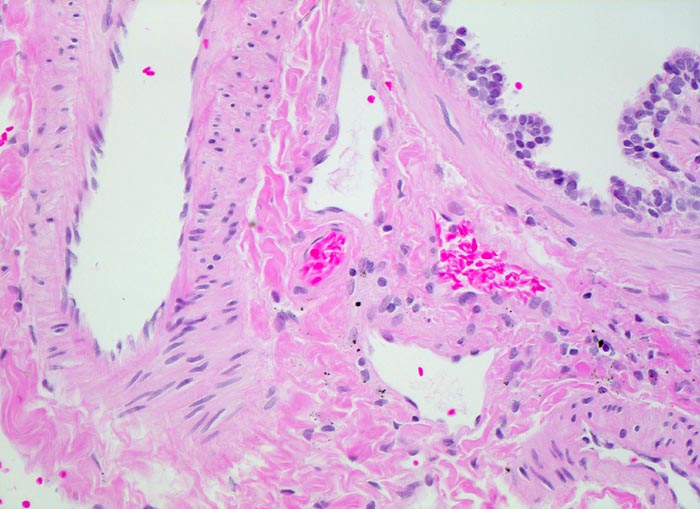

Das morphologische Bild ist äusserst variabel. Je nach Abwehrlage, Art und Geschwindigkeit der Ausbreitung entstehen unterschiedlich grosse, teils geschichtete Herde mit unterschiedlichem Grad an Epitheloidzellreaktion, zentraler Nekrose bzw. Vernarbung. Rein produktive Granulome ohne Nekrosen sind Zeichen guter Abwehrlage. Der Begriff Verkäsung bezieht sich auf den makroskopischen Aspekt von Nekrosen, der an Frischkäse erinnert. Exsudative nekrotisierende Granulome entstehen bevorzugt bei schlechter Abwehrlage. In späteren Stadien der Lungentuberkulose unterscheidet man produktive Phthisen mit azinös nodösen Gruppen von bronchogen entstandenen gering verkäsenden Streuherden (Präparat), zirrhotische Phthisen mit gering verkäsenden stark vernarbenden Herden und exsudative Phthisen bei schlechter Abwehrlage. Bei letzterer steht die Verkäsung im Vordergrund. Die bakterienreichen Herde entstehen teils hämatogen, teils bronchogen. Verkäsende Herde sind Ausgangspunkt für die Kavernenbildung. Kavernen stellen die wichtigste Quelle für die bronchogene Streuung dar.

• Tuberkulöse Herde ausgehend von vollständig oder partiell entzündlich zerstörten Bronchiolen in unmittelbarer Nachbarschaft von Arterien.

• Granulome mit zentraler käsiger Nekrose mit Kerntrümmern umgeben von einem Epitheloidzellwall und einem äusseren blauen Saum von Lymphozyten.

• Schlanke spindelige Epitheloidzellen und einzelne Riesenzellen vom Langhanstyp mit peripher hufeisenförmig angeordneten Kernen.